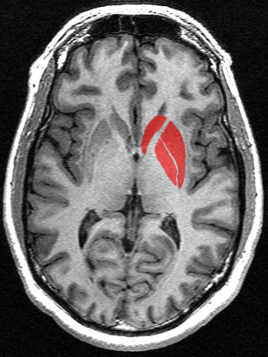

Esta ubicado en las paredes de los hemisferios cerebrales y en el se encuentran los centros de correlación y coordinación que regulan el ritmo de los movimientos, expresiones faciales durante la comunicación.

Está relacionado con la memoria, atención, instintos sexuales, emociones (por ejemplo placer, miedo, agresividad), personalidad y la conducta.

El sistema límbico incluye:

El tálamo un centro de relevo que controla la atención por el que pasan estímulos aferentes que llegan a la conciencia.